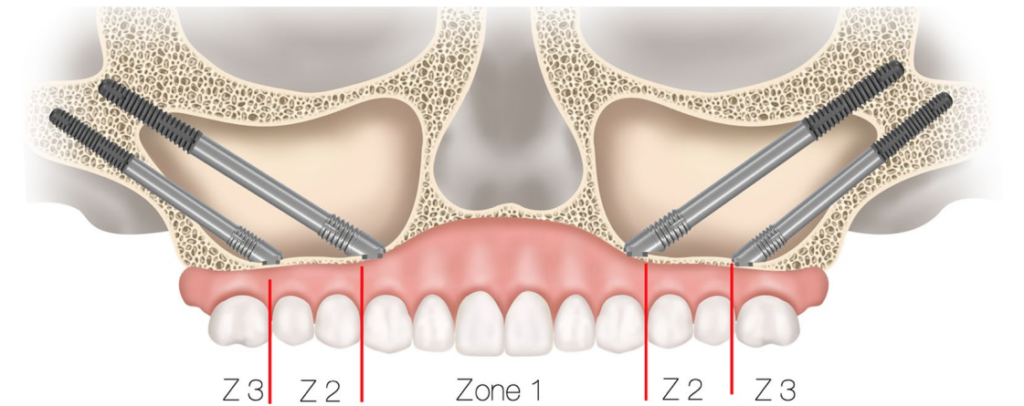

2.5.2. ザイゴマインプラント

ザイゴマインプラントは、「サイナススロットアプローチ」とエクストラサイナス技法を組み合わせて使用し、最適なインプラント固定と補綴的支持を得た(Figure 6)

エクストラマキシラリー法によるザイゴマインプラント埋入

頬骨へのドリリングは、回転数600 rpmに制御されたインプラント用ハンドピースを用いて行われた。その後、Nobel Biocare社製のザイゴマインプラント(TiUnite表面、45度アングル、直径4.3 mm)が埋入された。インプラントの長さは患者ごとの解剖学的条件に基づき、30 mmから52.5 mmの範囲で選択された。